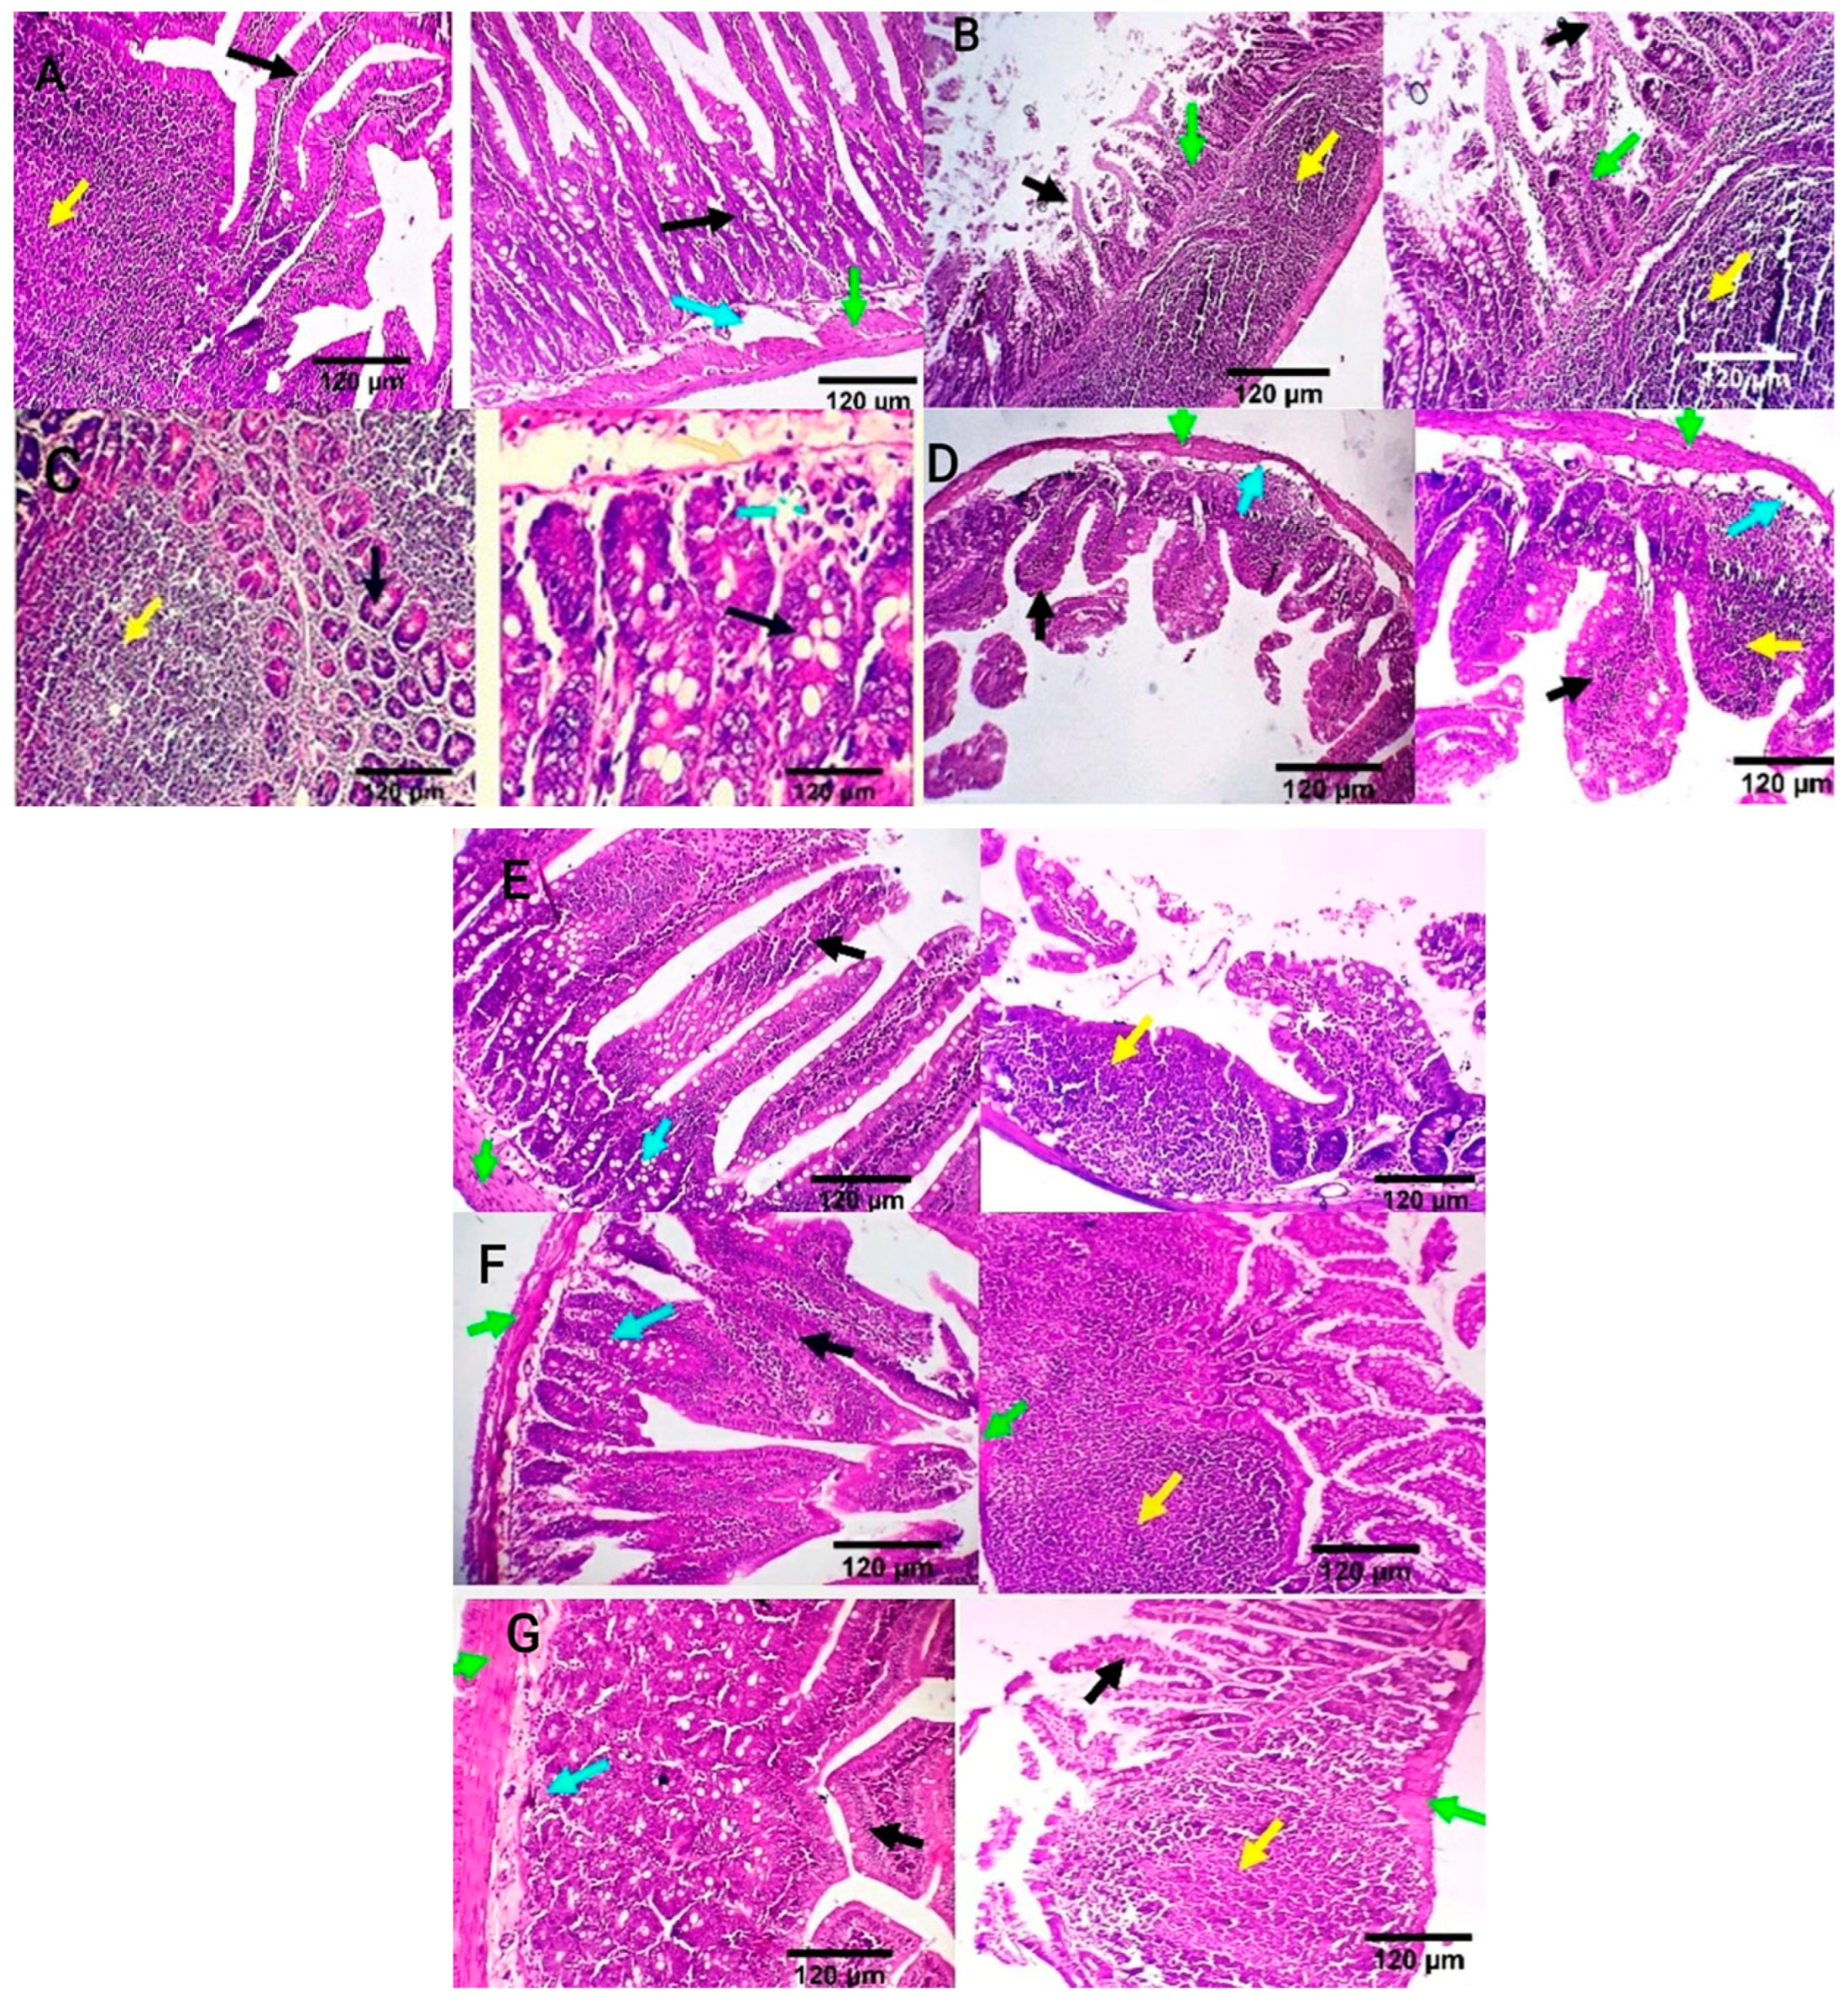

Intestinal tissue of the negative control group showed normal mucosal villi comprising absorptive columnar epithelium with a variable number of goblet cells and normal Peyer’s patches, submucosa, and muscular coat (Figure 6A). Meanwhile, in the positive control group, intestinal sections showed villous necrosis, mucosal leucocytic infiltration, and moderate lymphoid hyperplasia of Peyer’s patch. Villous atrophy with goblet cell metaplasia was also detected (Figure 6B). The ciprofloxacin-treated group displayed normal jejunal mucosa, normal submucosal glands, and mildly reactive Peyer’s patch. A few lymphocytes are seen in the submucosa (Figure 6C). CIP+OB-LNPs and CIP+LS-LNPs-treated groups showed a variable number of goblet cells and a moderately reactive Peyer’s patch. In addition, normal jejunal mucosal villi and a few lymphocytes are seen in the villous mucosa (Figure 6D,E). Both the OB-LNPs and LS-LNPs-treated groups revealed normal villi, comprising a variable number of goblet cells and a mildly reactive Peyer’s patch. The submucosa and muscular coat are apparently normal (Figure 6F,G).

Figure 6.

Photomicrograph from the ileum and jejunum of rats using H&E staining at 7th day post infection with S. Typhimurium. (A) noninfected and nontreated rats showing normal mucosal villi comprising absorptive columnar epithelium with variable number of goblet cells (black arrow), normal Peyer’s patch (yellow arrow), normal submucosa (light blue arrow), and muscular coat (green arrow). (B) infected, non-treated rats showing villous necrosis (black arrows), mucosal leucocytic infiltration (green arrows), and moderate lymphoid hyperplasia of Peyer’s patch (yellow arrows). (C) rats were infected and treated with 45 mg/kg CIP (ciprofloxacin) orally once daily for 5 days. The ileum revealed normal submucosal glands (black arrow) and mildly reactive Peyer’s patch (yellow arrow). The jejunum revealed normal jejunal mucosal villi comprising absorptive columnar epithelium with a variable number of goblet cells (black arrow), and few lymphocytes are seen in the submucosa (light blue arrow). (D) rats were infected and received CIP+OB-LNPs (45 mg/kg bw + 2.5 mL/kg bw). The jejunum and ileum show normal mucosal villi comprising absorptive columnar epithelium with a variable number of goblet cells, occasional lymphocytic infiltration (black arrow), and normal Peyer’s patch (yellow arrow), beside normal submucosa (light blue arrows) and muscular coat (green arrow). (E) rats were infected and treated with CIP+LS-LNPs (45 mg/kg bw + 2.5 mL/kg bw) showing normal mucosal villi comprising absorptive columnar epithelium with variable number of goblet cells (black arrow) and normal Peyer’s patch (yellow arrow), beside normal submucosa (light blue arrows) and muscular coat (green arrow). Ileal villi of some sections appear moderately stunted (white stars). (F) rats were infected and treated with OB-LNPs (2.5 mL/kg bw), showing normal mucosal villi comprising absorptive columnar epithelium with a variable number of goblet cells and occasional epithelial stratification (black arrow), moderately reactive Peyer’s patch (yellow arrow), normal submucosa (light blue arrows), and muscular coat (green arrow). (G) rats were infected and treated with LS-LNPs (2.5 mL/kg bw) daily for 5 days, showing normal mucosal villi with variable number of goblet cells (black arrow), normal Peyer’s patch (yellow arrow), normal submucosa (light blue arrows), and muscular coat (green arrow).